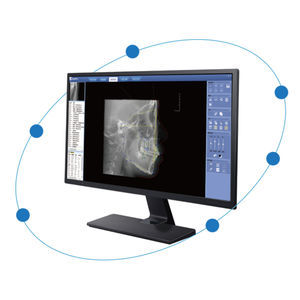

... Diseñado para cirujanos orales y maxilofaciales, el software OMS Imaging de Carestream Dental cuenta con todas las herramientas necesarias para realizar un diagnóstico seguro. Diseñado para cirujanos ...

... Mejora la eficacia del trabajo y la precisión del diagnóstico con un flujo de trabajo intuitivo y cómodo. Proporciona un visor de imágenes y un control de imágenes optimizados. Flujo de trabajo sencillo y UI/UX intuitivo Función de informe ...